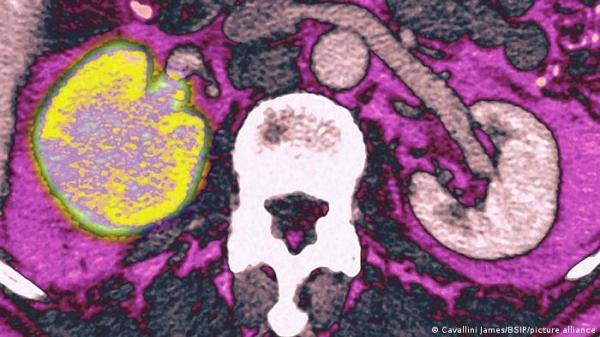

اكتشاف الجينات المرتبطة بأشرس أنواع سرطان الكلى

علماء يبتكرون أسلوبا لاكتشاف سرطان الكبد بناء على قطرة دم واحدة